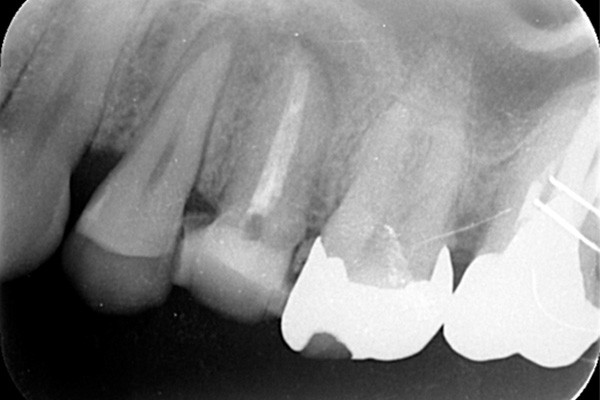

左のレントゲンでは破折したかどうかはわからないが、虫歯になっている部分をとっていくと歯が割れているのがはっきりとわかりました。

歯が割れるケースで多いのが金属の土台(メタルコア)が入っている場合です。特に根の中に長いものが入っていると、歯を割る力が強くかかるため、割れることが多いです。